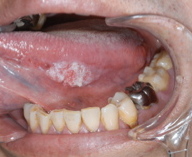

舌がん写真Ⅰ          舌がんしゃしんⅡ

画像引用:東京医科歯科大学顎口腔外科

初期の自覚症状はほとんどなく、舌がほんの少しざらざらしたり、

白い斑 点が見られるくらいです。